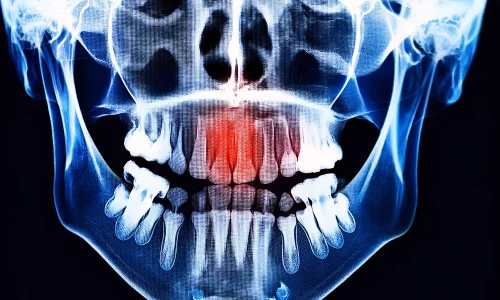

Grinding dei Denti (Bruxismo) e Ortodonzia: Posso Avere Apparecchi o Aligners Trasparenti se Digrano i Miei Denti?

Il bruxismo (digrignare i denti) e l'ortodonzia (trattamento con apparecchio o allineatori trasparenti) si verificano insieme nel medesimo paziente molto più frequentemente di quanto si pensi. Soprattutto nelle persone di età compresa tra i 25 e i 45 anni che sono sotto stress intenso, trascorrono ore davanti a un computer e hanno una scarsa qualità del sonno, possono presentarsi sia il bruxismo che un problema ortodontico.

2. Effetti del digrignare i denti sui denti e sull'articolazione mandibolare

Il digrignare i denti lieve e a breve termine potrebbe non causare problemi significativi. Tuttavia, nel bruxismo cronico, i problemi comunemente osservati includono:

1. Usura e abrasione dentale.

2. Fessure e fratture dentali.

3. Fratture in otturazioni e corone.

4. Accorciamento delle lunghezze dentali.

La Dott.ssa Begüm Ulaşan presso Milim Dental Bursa, quando pianifica l'ortodonzia per un paziente sospettato di bruxismo, valuta attentamente:

1. Segni di usura dentale.

2. Tenerezza muscolare.

3. Risultati ATM.

Questo perché l'obiettivo non è solo allineare i denti, ma rendere il sistema mandibolare più equilibrato e protetto.